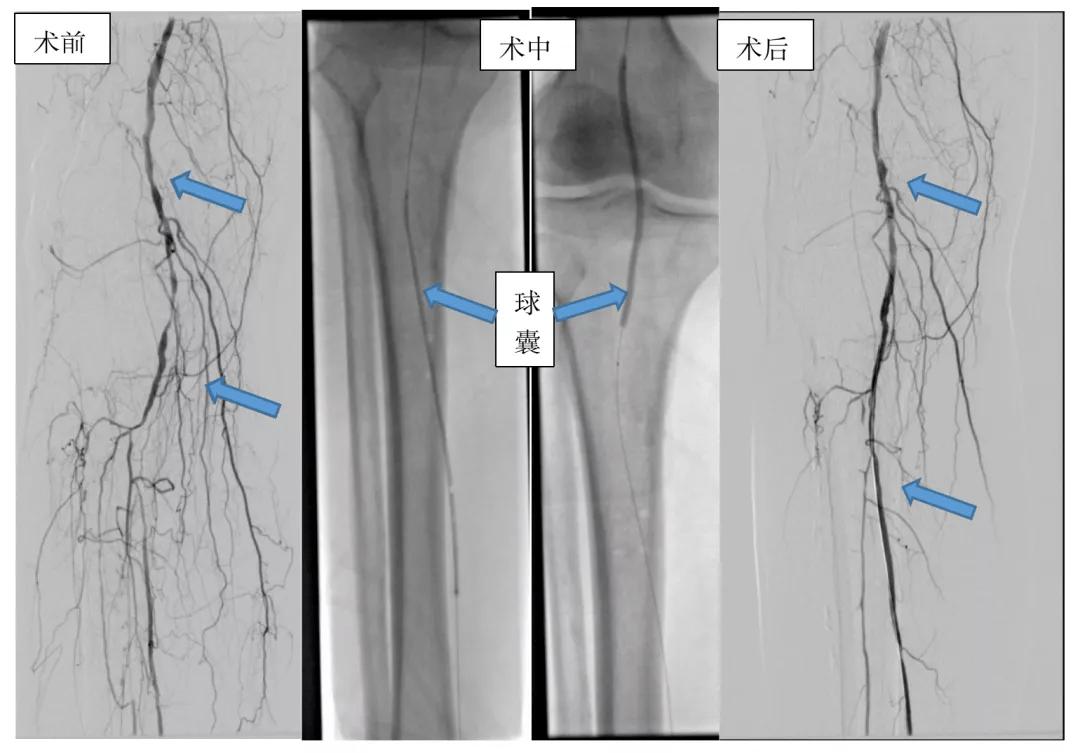

*图示 介入手术开通前右侧腘动脉和胫后动脉多发狭窄闭塞,经过球囊对狭窄段进行分段扩张,术后复查狭窄血管开通良好。